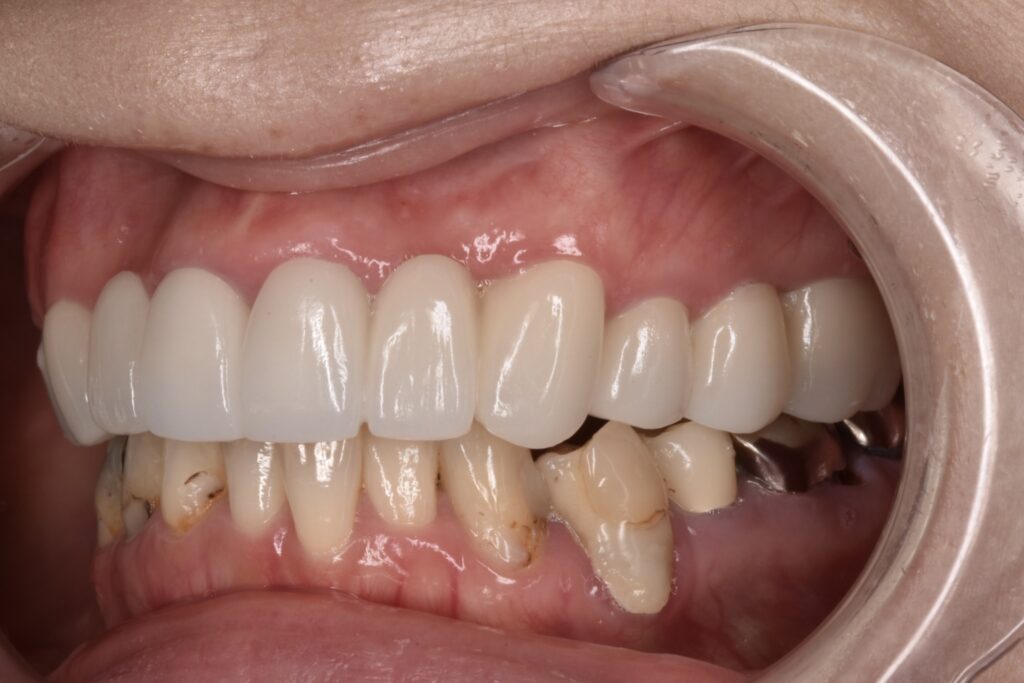

上顎セラミック治療後

上の両奥歯3本ずつはさくらセラミックプラン 前歯6本匠セラミックプランで治療させて頂きました。

セラミック本留前の仮歯でのレントゲン写真です。下の歯は破折があり抜歯してインプラントをしています。